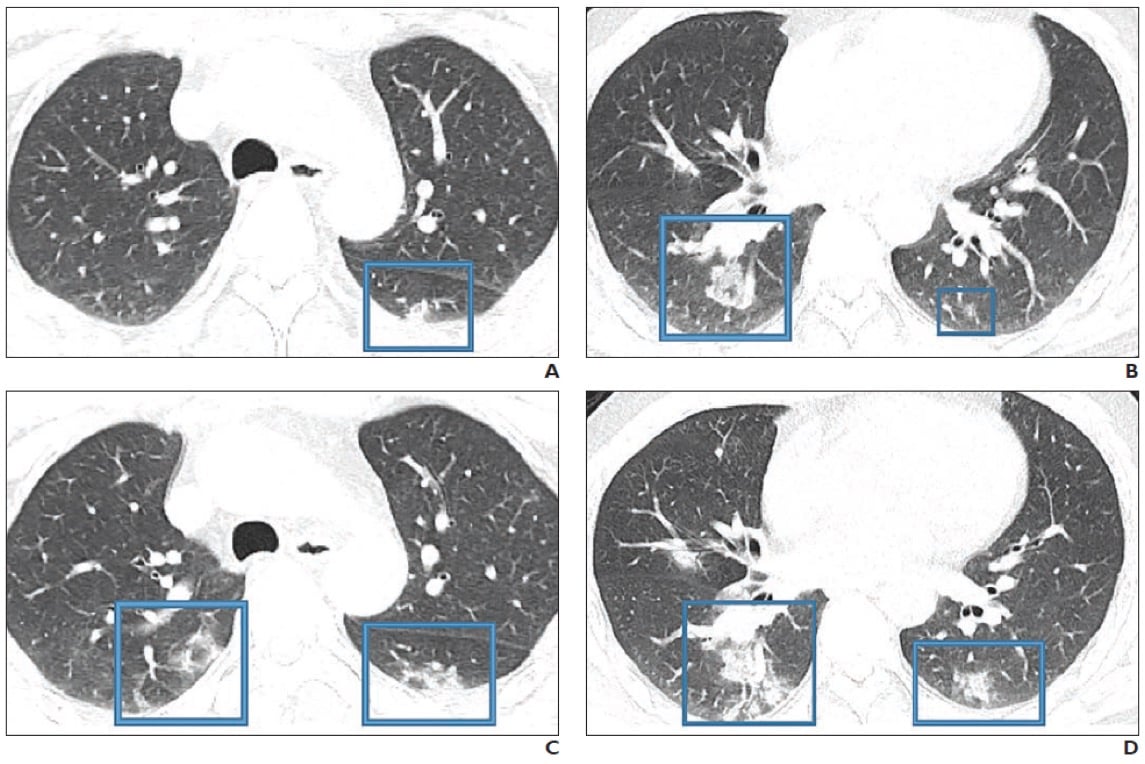

A 47-year-old Chinese man with two-day history of fever, chills, productive cough, sneezing, and fatigue who presented to emergency department. A and B, Initial CT images obtained show small round areas of mixed ground-glass opacity and consolidation (rectangles) at level of aortic arch (A) and ventricles (B) in right and left lower lobe posterior zones. C and D, Follow-up CT images obtained 2 days later show progression of abnormalities (rectangles) at level of aortic arch (C) and ventricles (D), which now involve right upper and right and left lower lobe posterior zones. Image courtesy of AJR.